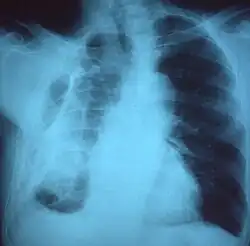

| Fibrothorax on chest x-ray | |

If a fibrothorax is severe, the thickening may restrict the lung on the affected side causing a loss of lung volume.[7] Additionally, the mediastinum may be physically shifted toward the affected side.[3] A reduction in the size of one side of the chest (hemithorax) on an X-ray or CT scan of the chest suggests chronic scarring.[6] Signs of the underlying disease causing the fibrothorax are also occasionally seen on the X-ray.[6] A CT scan may show features similar to those seen on a plain X-ray.[7] Lung function testing typically demonstrates findings consistent with restrictive lung disease.[6]

Extensive left-sided fibrothorax -

Chest radiograph displaying inhomogeneous opacification of the left half of the chest that is fibrothorax -